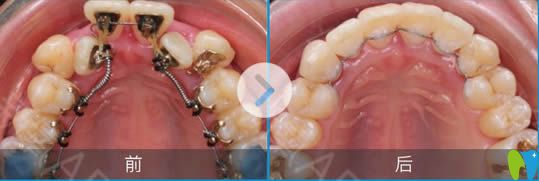

上頜牙矯正后前后對(duì)比效果:

下頜牙矯正后前后對(duì)比照: